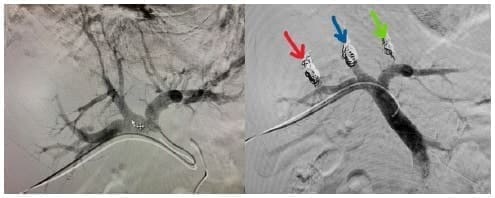

Debido al compromiso neoplásico de la vía biliar, se resecó y se reconstruyó mediante una colangioyeyunostomía de ductos separados en Y de Roux (figura 7).

Figura 7. Reconstrucción en Y de Roux por medio de colangio- yeyunostomía de ductos sector posterior derecho (flecha verde) y lateral izquierdo (flecha azul) por separado. Vena Suprahepática derecha completamente disecada luego de la resección del sector anterior derecho.

El tiempo quirúrgico fue de 480 minutos, el sangrado de 1000 ml, y el tiempo de la maniobra de Pringle de 43 minutos (cuatro pinzamientos). El paciente presentó fuga biliar tipo B que se manejó con drenaje percutáneo y antibióticos de amplio espectro por 14 días. La hospitalización duro 23 días, 12 de ellos en cuidado crítico.